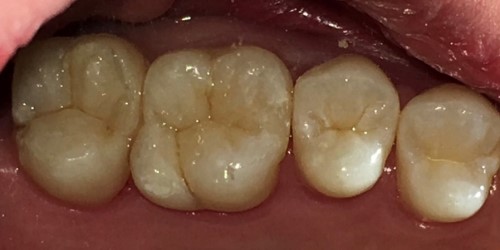

CASE03ダイレクトボンディング

-

Before

After

| 主訴 | できるだけ歯を削らずに銀歯を白くしたい。 |

|---|---|

| 治療方法 | 銀歯を除去した後、ダイレクトボンディング法によりコンポジットレジンを用いて修復した。 |

| 治療期間 | 1回 |

| リスク | 長年使用することによる着色。咬合圧が強い場合破折することがある。 |

| 費用 | 55,000円×2(税込み) |